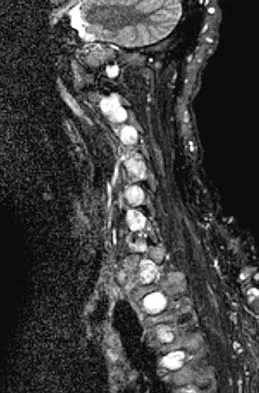

Question 37

Figures 5a and 5b show the radiograph and MRI scan of a patient who has severe mechanical neck pain but no neurologic problems. Biopsy and work-up show the lesion to be a solitary plasmacytoma. Treatment should consist of

Explanation